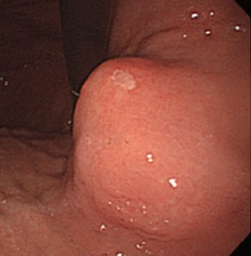

Gastroscopy. Green arrows: orifice of the gastrocolic fistula (Courtesy Dr. V. Penopoulos)